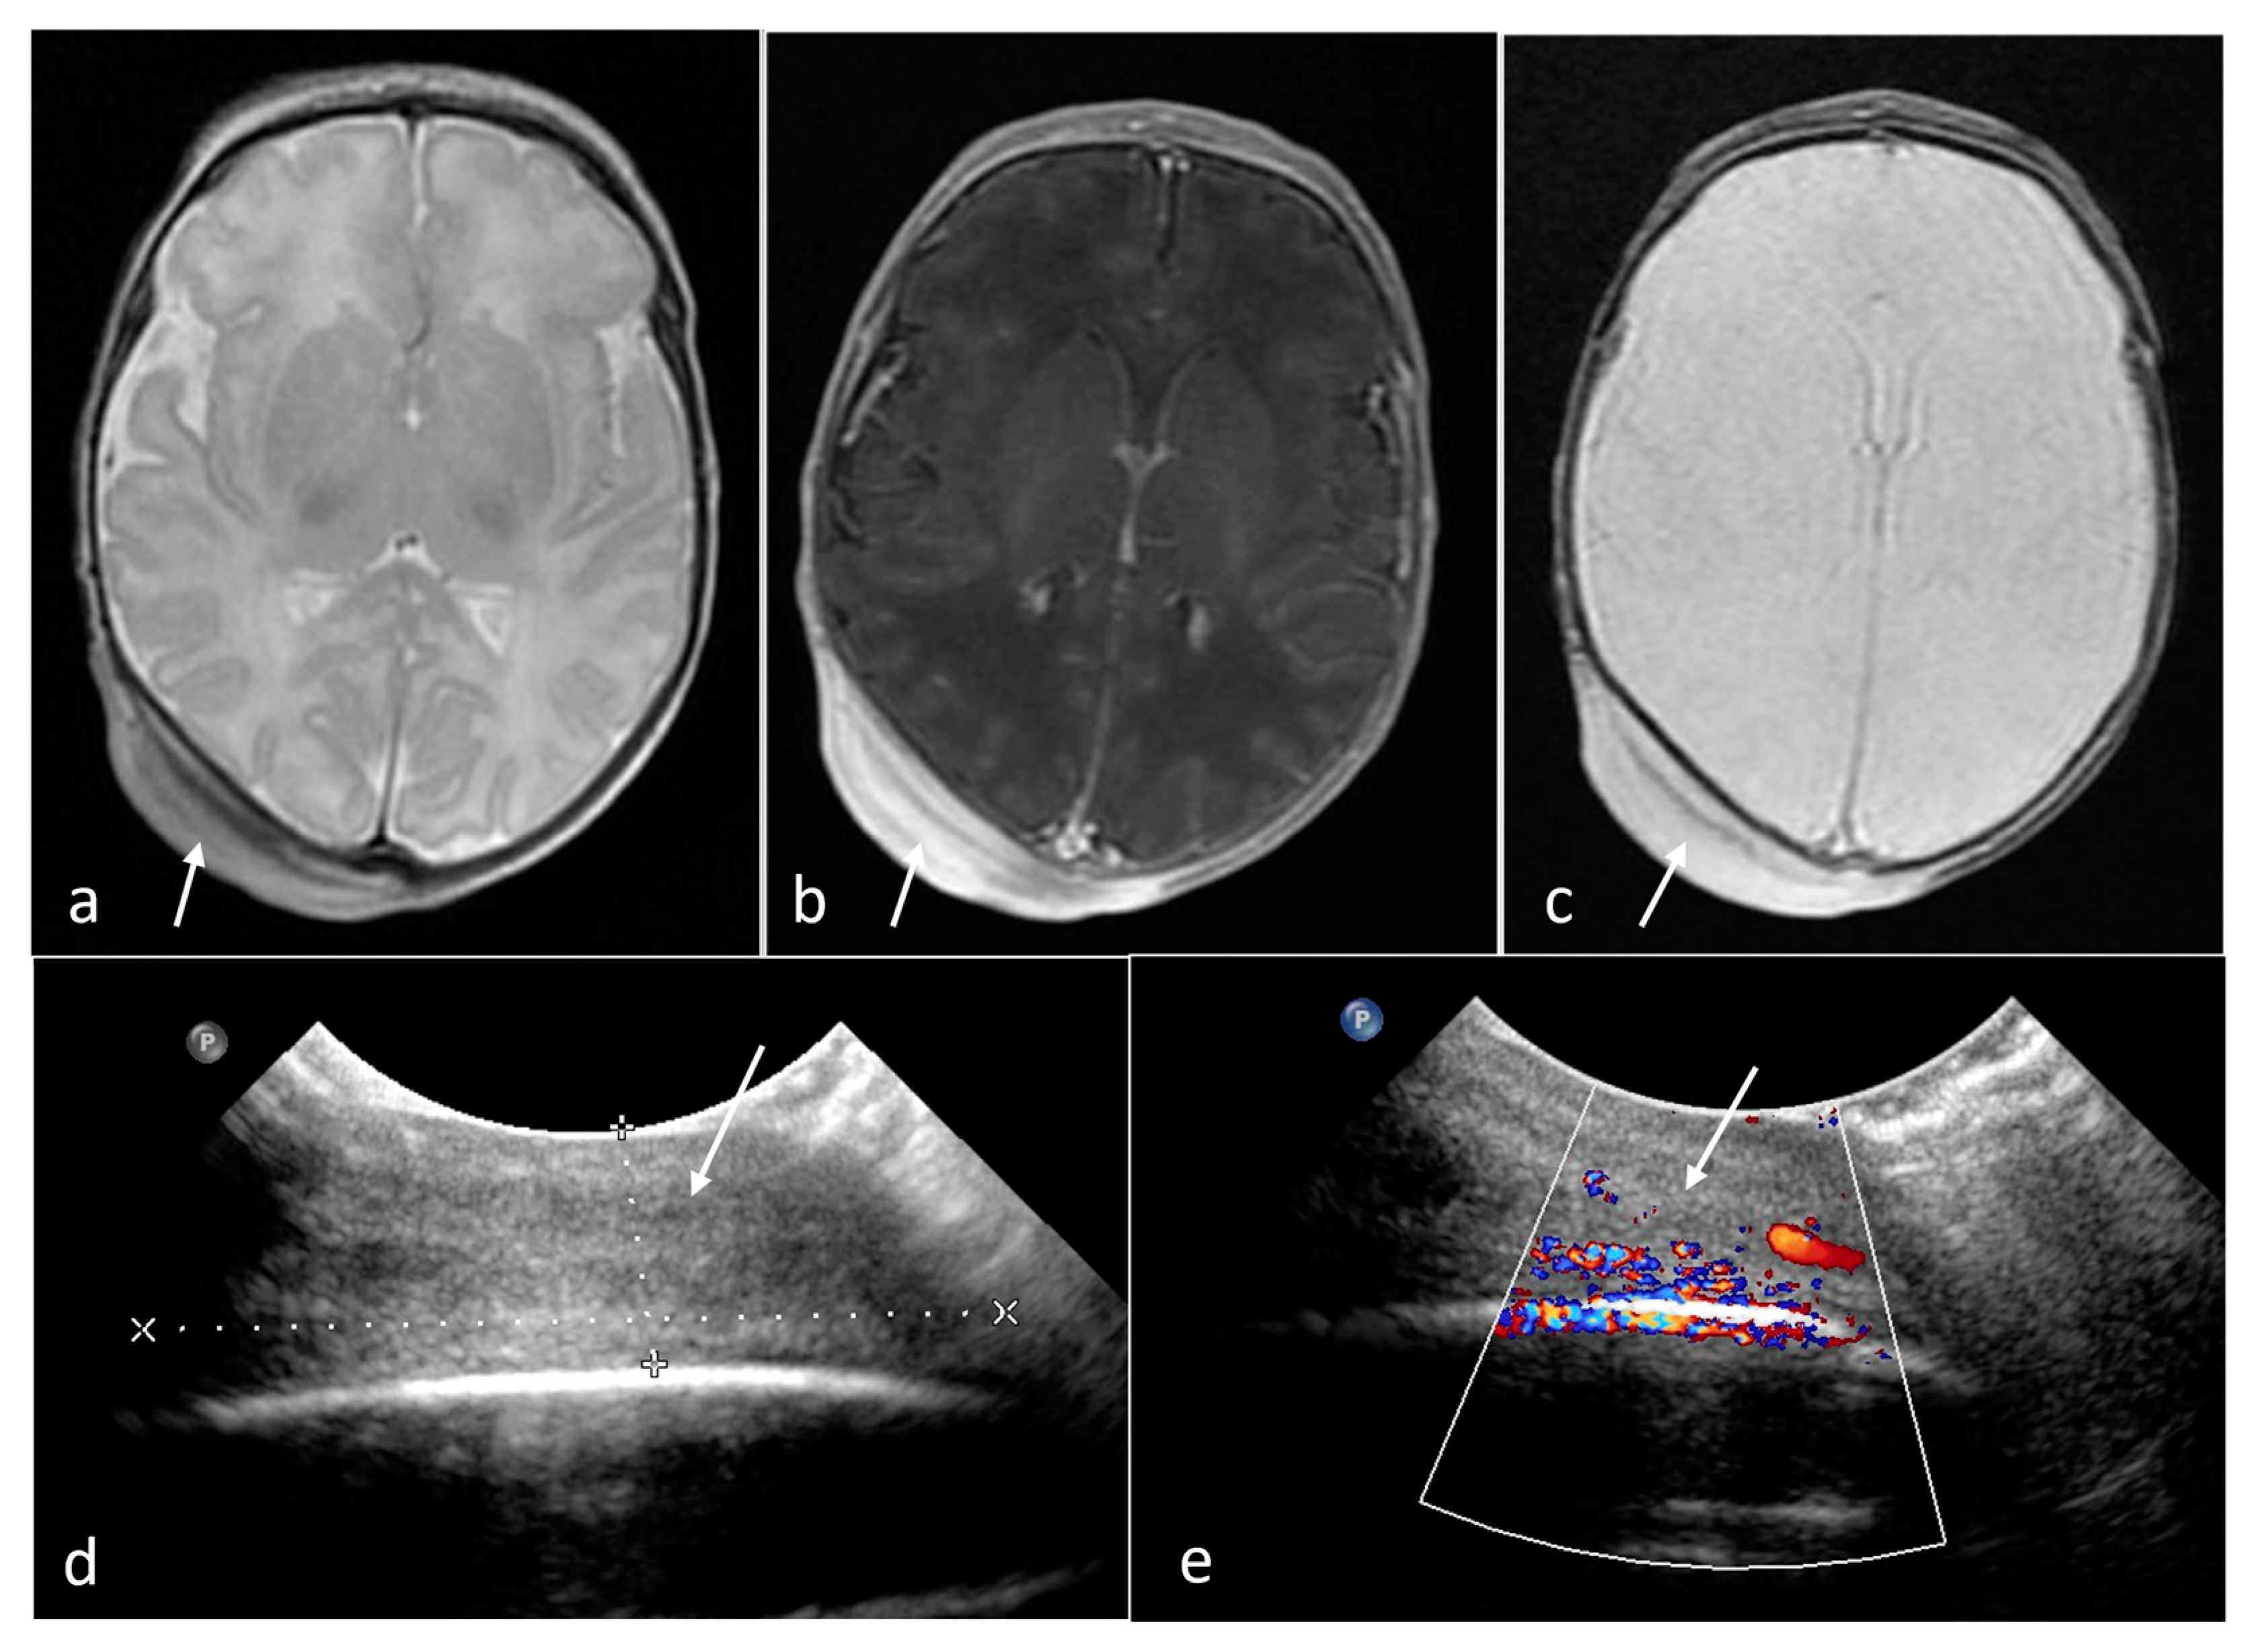

| Subependymal giant cell astrocytoma | foramen of Monro | 6 | 0.74 [0.59–0.89] | no | Solid | yes (2/2) | N/A |

- Goh, S.; Butler, W.; Thiele, E.A. Subependymal giant cell tumors in tuberous sclerosis complex. Neurology 2004, 63, 1457–1461. [Google Scholar] [CrossRef]

- Goergen, S.K.; Fahey, M.C. Prenatal MR Imaging Phenotype of Fetuses with Tuberous Sclerosis: An Institutional Case Series and Literature Review. AJNR Am. J. Neuroradiol. 2022, 43, 633–638. [Google Scholar] [CrossRef] [PubMed]

- Bekiesinska-Figatowska, M.; Sobieraj, P.; Pasieczna, M.; Szymkiewicz-Dangel, J. Early diagnosis of tuberous sclerosis complex: Prenatal diagnosis. AJNR Am. J. Neuroradiol. 2023, 44, 1070–1076. [Google Scholar] [CrossRef]